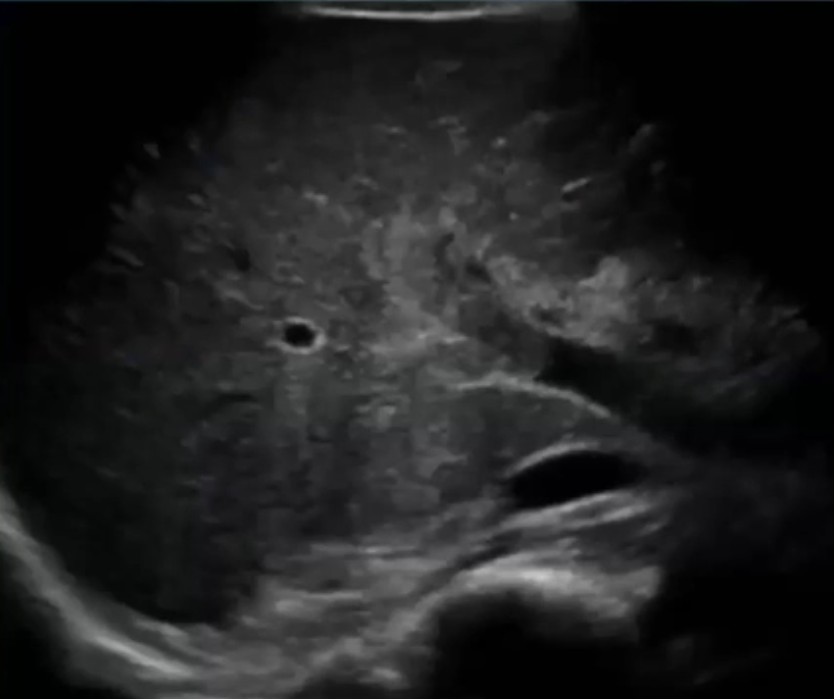

伴有腹痛及肠道缺血的情况 使用抗凝剂治疗后,大多数患者会有所好转,但有 10% - 20% 的患者治疗无效。 对于这些患者,应进行经皮经肝的血栓性门静脉(PV)穿刺、溶解、抗凝治疗,通常效果是足够的,越早发现病情越好。 经颈静脉的通路不建议作为首选方法,因为接受溶栓治疗的患者其并发症风险较高。 使用 t-PA 治疗后,肝内血流情况良好,且可见外周门静脉分支血管,继续使用 t-PA,并进行抗凝治疗。

急性病例,已有肠道缺血的迹象,经皮穿刺入路,尿激酶溶栓(t-PA),血流不畅,转为经颈静脉肝内门体分流术(TIPS),抗凝治疗